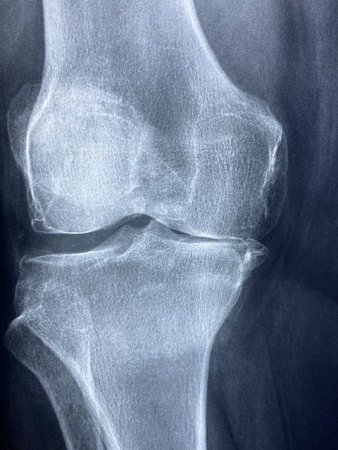

২০১৭ সাল থেকে বাম হাঁটু নিয়ে ভুগতেছি। পঙ্গু হাসপাতাল থেকে পিজি হাসপাতাল পর্যন্ত অনেক ডাক্তারের কাছেই গিয়েছি কিন্তু কাজ হয় নাই বরঞ্চ আরো হাঁটুর ব্যাথায় কিছুদিন লাঠি ভর দিয়ে হাঁটতে হয়েছে। হাটলেই হাঁটু ফুলে যায় এবং প্রচন্ড ব্যাথা করে। অবশেষে গেলাম বেঙ্গালোরে। মজুমদার সাউ হাসপাতালের অর্থপেডিকসের সিনিয়র ডাক্তার দেখানোর পরে তিনি এক্সরে দেখে বললেন, আপনার হাঁটু ক্ষয় হয়েছে এটা রিপিয়ের করতে হবে। বললাম কিভাবে রিপিয়ার করবেন? বলল, হাঁটু কেটে প্লাস্টিকের হাঁটু লাগাতে হবে। বললাম টাকা লাগবে কত? বলল, তিন লাখ রুপি।

লুধুয়া বলেছেন: হাঁ এক্স ray তে দেখা যাসছে knee এর medial epicondyal স্পেস কমে গেছে। আপনার Osteo arthritis হয়েছে।

প্রামানিক বলেছেন: স্পেসের কারণেই আমি ভুগতেছি। এখন এই স্পেসের সম্যাটা কমছে কিনা এক্সরে করে দেখা হয় নাই।